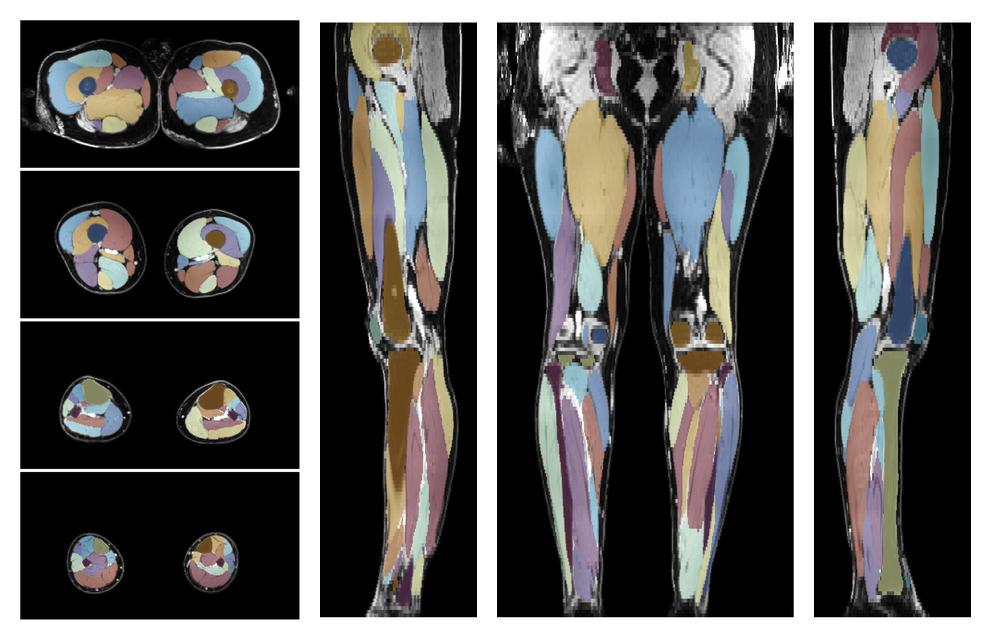

Muscle segmentation

Convolution neural network based (UNET) fiber automated muscle segmentation, for information look here».

• 3D volume render of automated muscle segmentation.

3D render of automated muscle segmentation labels generated using a CNN UNET.

• Automated muscle and bone segmentation.

Overlay of automated muscle segmentation labels on dixon water image.